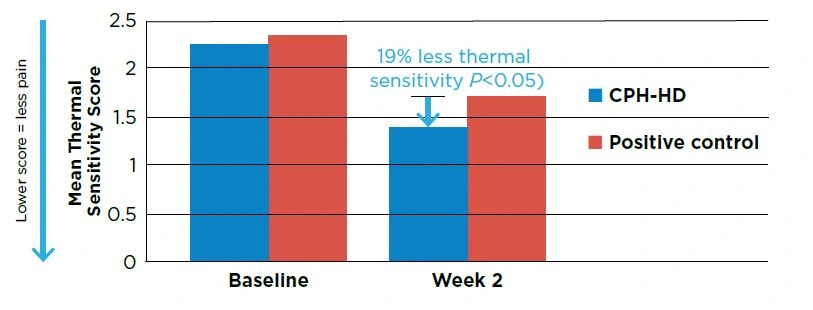

KEY CLINICAL RESULTS

A 2-step stannous fluoride dentifrice and whitening gel system (Crest® PROHEALTH™ [HD]™, CPH-HD) provided superior tactile and thermal sensitivity relief (P<0.05) versus a positive control potassium nitrate dentifrice (Sensodyne® Extra Whitening). Both groups provided a significant benefit relative to baseline for both measures (P<0.0001). See Figures 1 & 2.

Seventy-two percent (72%) of teeth tested in the CPH-HD group experienced an improvement in thermal sensitivity compared to 53% in the positive control group. Fifty-five percent of teeth tested using the CPH-HD product experienced relief from tactile sensitivity compared to 37% for the positive control.

Figure 1. Mean thermal sensitivity scores at Baseline and Week 2. N=69

Figure 2. Mean tactile sensitivity scores at Baseline and Week 2. N=69